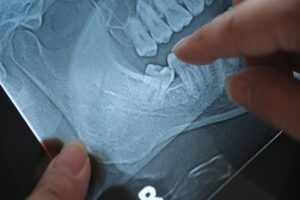

While some people have enough space for wisdom teeth to come in normally, many (or even most) do not. When wisdom teeth lack sufficient space to develop, they may become impacted. This essentially means that they can’t break through the gums or jawbone to erupt in the proper position. This can lead to several problems for your oral health.

In severe cases, fluid-filled cysts can form around impacted wisdom teeth. These cysts can gradually erode surrounding bone and damage neighboring tooth roots. Though rare, cysts that go untreated for long periods can cause significant jawbone loss and may require surgical repair.